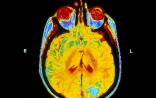

尽管并没有随机临床试验显示全脑放疗能改善患者的生活质量或存活率,但是全脑放疗仍广泛用于肺癌脑转移患者的治疗。近日,发表在《柳叶刀》杂志上的研究称:一个超过500例患者的试验发现,全脑放疗对已经扩散到脑部的肺癌患者是没有好处的,它并没有比其他形式的治疗延长或改善患者的生活质量。